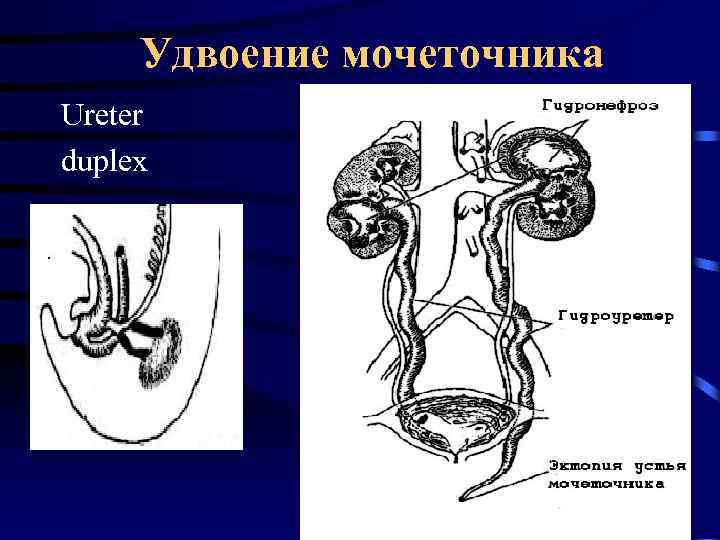

Удвоение мочеточника Ureter duplex

Удвоение мочеточника Ureter duplex